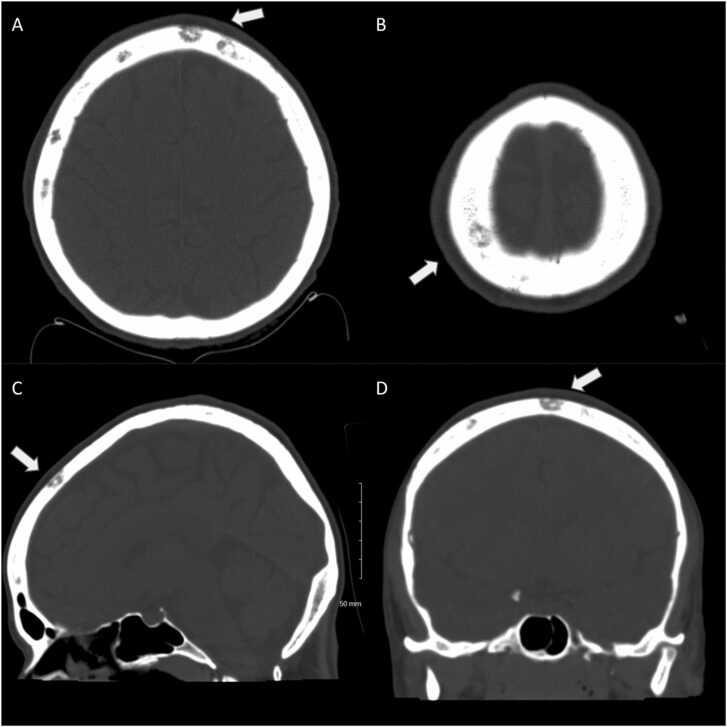

We report a case of calvarial lytic lesions in neurosyphilis with ocular involvement. A 42-year-old woman with a past medical history of polysubstance abuse presented with recent bilateral vision loss. CT revealed numerous calvarial lytic lesions and multiple myeloma was initially suspected. Syphilis screening with RPR and confirmative CSF studies were positive for active infection. The patient was treated with Penicillin G and demonstrated clinical improvement. The objective of this study was to provide insight into a rare manifestation of syphilis with osseous involvement and encourage further discourse into establishment of standards of care for syphilitic osteomyelitis. There exist no evidence-based guidelines regarding optimal treatment route and duration, role of bone biopsy, determination of therapeutic impact, and threshold for surgical intervention in the management of syphilitic osteomyelitis.

我们报告一例伴有眼部受累的神经梅毒颅骨溶骨性病变病例。一名有多种药物滥用病史的42岁女性,近期出现双侧视力丧失。CT显示颅骨有多处溶骨性病变,最初怀疑为多发性骨髓瘤。梅毒血清学试验(RPR)筛查及脑脊液确诊检查均显示活动性感染呈阳性。该患者接受了青霉素G治疗,临床症状有所改善。本研究的目的是深入了解梅毒累及骨骼这一罕见表现,并鼓励进一步探讨制定梅毒骨髓炎的护理标准。关于梅毒骨髓炎的最佳治疗途径和疗程、骨活检的作用、治疗效果的判定以及手术干预阈值等方面,目前尚无循证指南。